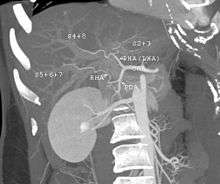

-

A CT scan in which the liver and portal vein are shown.

With the recent advances of noninvasive imaging, living liver donors usually have to undergo imaging examinations for liver anatomy to decide if the anatomy is feasible for donation. The evaluation is usually performed by multidetector row computed tomography (MDCT) and magnetic resonance imaging (MRI). MDCT is good in vascular anatomy and volumetry. MRI is used for biliary tree anatomy. Donors with very unusual vascular anatomy, which makes them unsuitable for donation, could be screened out to avoid unnecessary operations.

MDCT image. Arterial anatomy contraindicated for liver donation

MDCT image. Portal venous anatomy contraindicated for liver donation

MDCT image. 3D image created by MDCT can clearly visualize the liver, measure the liver volume, and plan the dissection plane to facilitate the liver transplantation procedure.